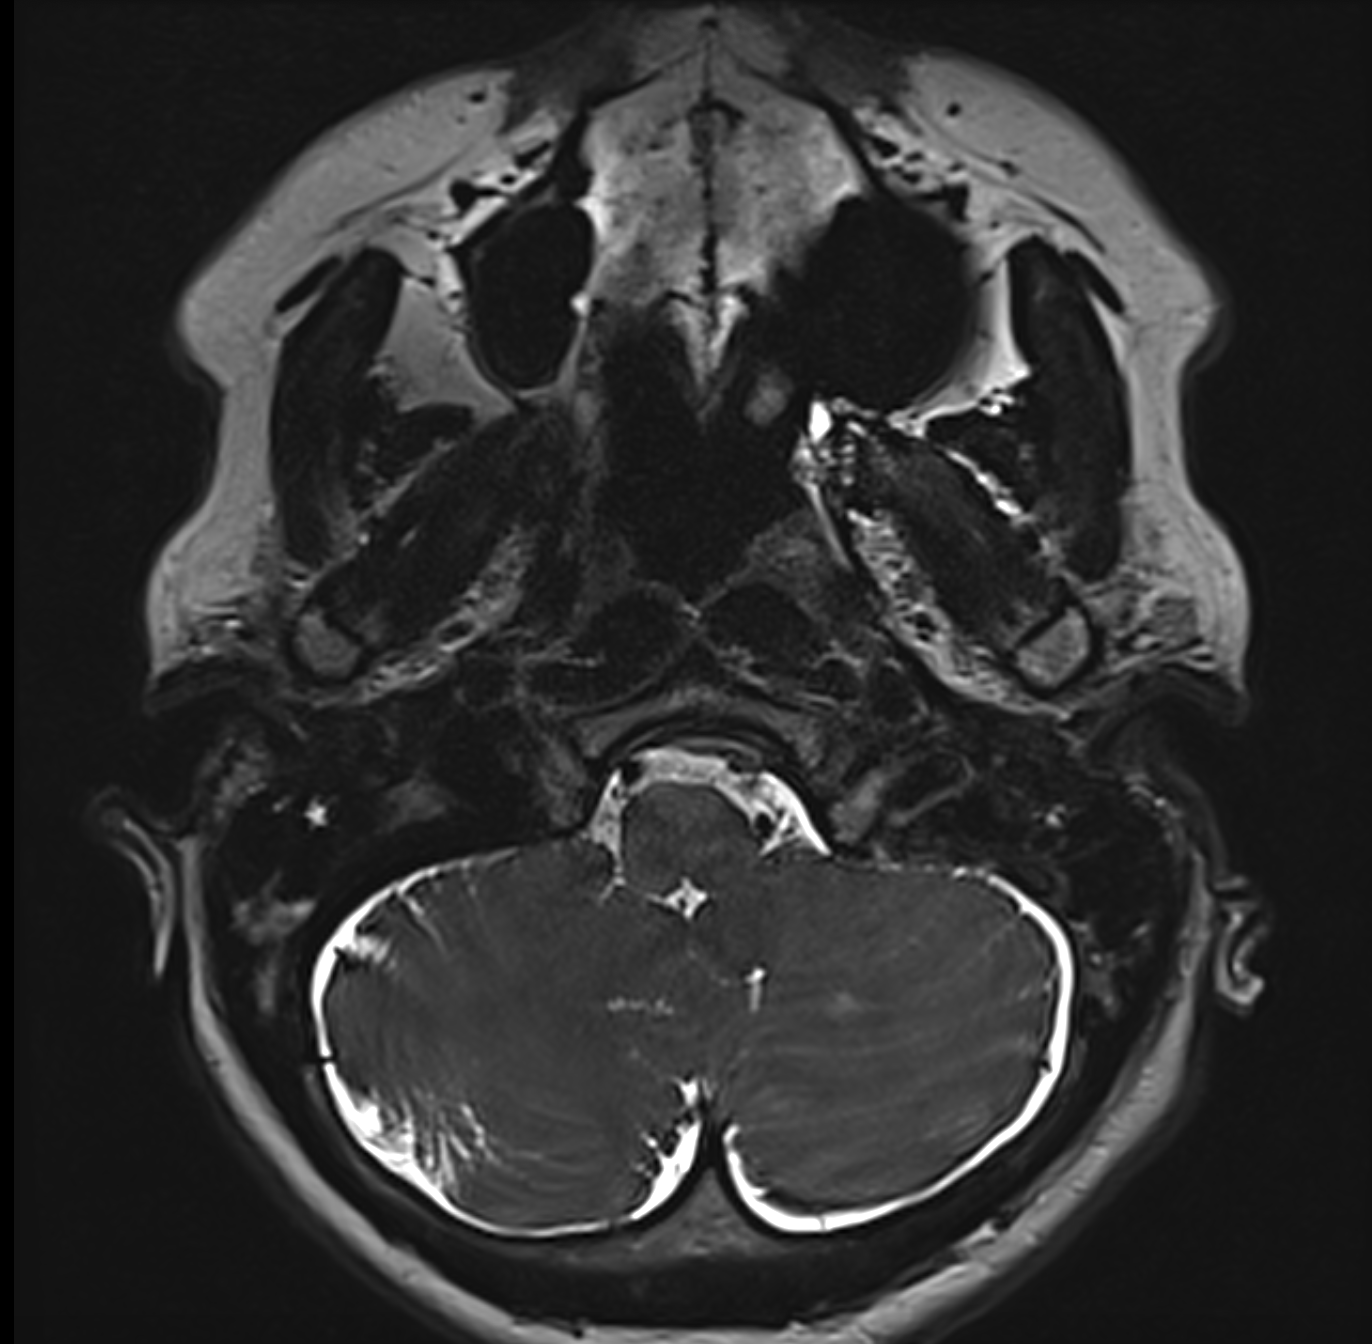

Este vorba despre o doamnă de 56 ani care a efectuat un RMN cerebral pentru a investiga un episod de pierdere a conștienței (care s-a dovedit a fi doar o lipotimie) și a descoperit că este purtătoarea unui meningiom de foramen magnum.

Tumora are baza de inserție largă pe dura mater antero-laterală stângă a joncțiunii cranio-spinale (foramen magnum) – antero-lateral stânga de trunchiul cerebral – este parțial calcificată, are dimensiuni de 36/29/31 mm și înglobează artera vertebrală stângă; la polul inferior este în contact cu nervul hipoglos (nervul cranian XII, care asigură inervația motorie a limbii); nervul spinal accesor (nervul cranian XI), care deservește mușchii trapez și sterno-cleido-mastoidian, trece pe fața posterioară a tumorii, iar nervii vag și hipoglos (nervii cranieni IX și X, care acționează mușchii laringelui și ai faringelui, esențiali pentru fonație și deglutiție) se află la polul superior al tumorii. Toate aceste contacte cu vase și nervi fac extrem de delicată intervenția chirurgicală, orice gest greșit putând avea consecințe grave pentru pacient. pe de altă parte, chiar dacă (bănuim) este vorba de o tumoră benignă, ea va crește în dimensiuni și va ajunge să înglobeze complet vasele de sânge și nervii din jur, punând presiune și pe trunchiul cerebral. În asemenea cazuri, cu cât faci operația mai repede, cu atât este mai bine pentru pacient (și pentru chirurg).